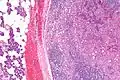

| Micrograph of an acinic cell carcinoma (right of image) and acinar glands (parotid gland - left of image). H&E stain. | |

Basophilic, bland cells similar to acinar cells. Growth pattern: solid - acinar cells, microcytic - small cystic spaces mucinous or eosinophilic, papillary-cystic - large cystic lined by epithelium, follicular - similar to thyroid tissue.

These tumors, which resemble serous acinar cells, vary in their behavior from locally aggressive to blatantly malignant.

Intermed. mag.